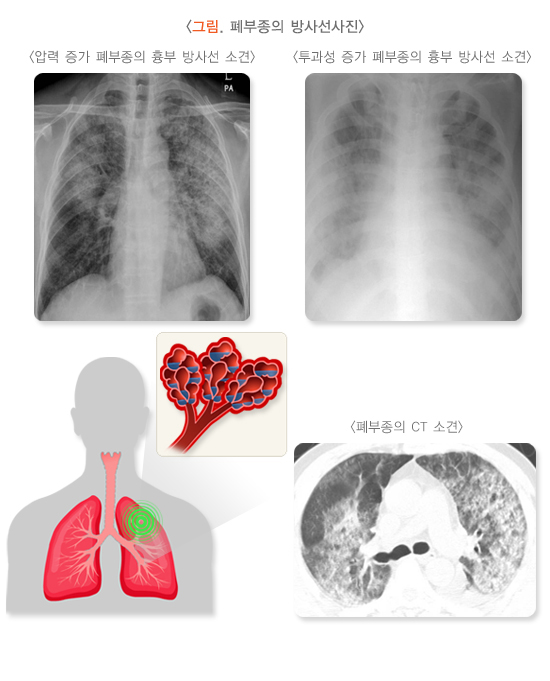

5. 흉부방사선 사진

원인 질환에 따라 심장 비대의 소견을 관찰할 수 있고, 좌심실 부전이 있는 경우 폐울혈 소견, 컬리 B(Kerley B)선이 나타나며, 심해지면 양쪽 폐에 뿌연 음영이 심장 주위를 중심으로 분포하고 늑막 삼출도 관찰됩니다. 심인성 폐부종에 비해 비심인성 폐부종이 일반적으로 더 심합니다. 경우에 따라 원인 감별을 위해 흉부 단층 촬영(CT)을 시행할 수 있습니다.